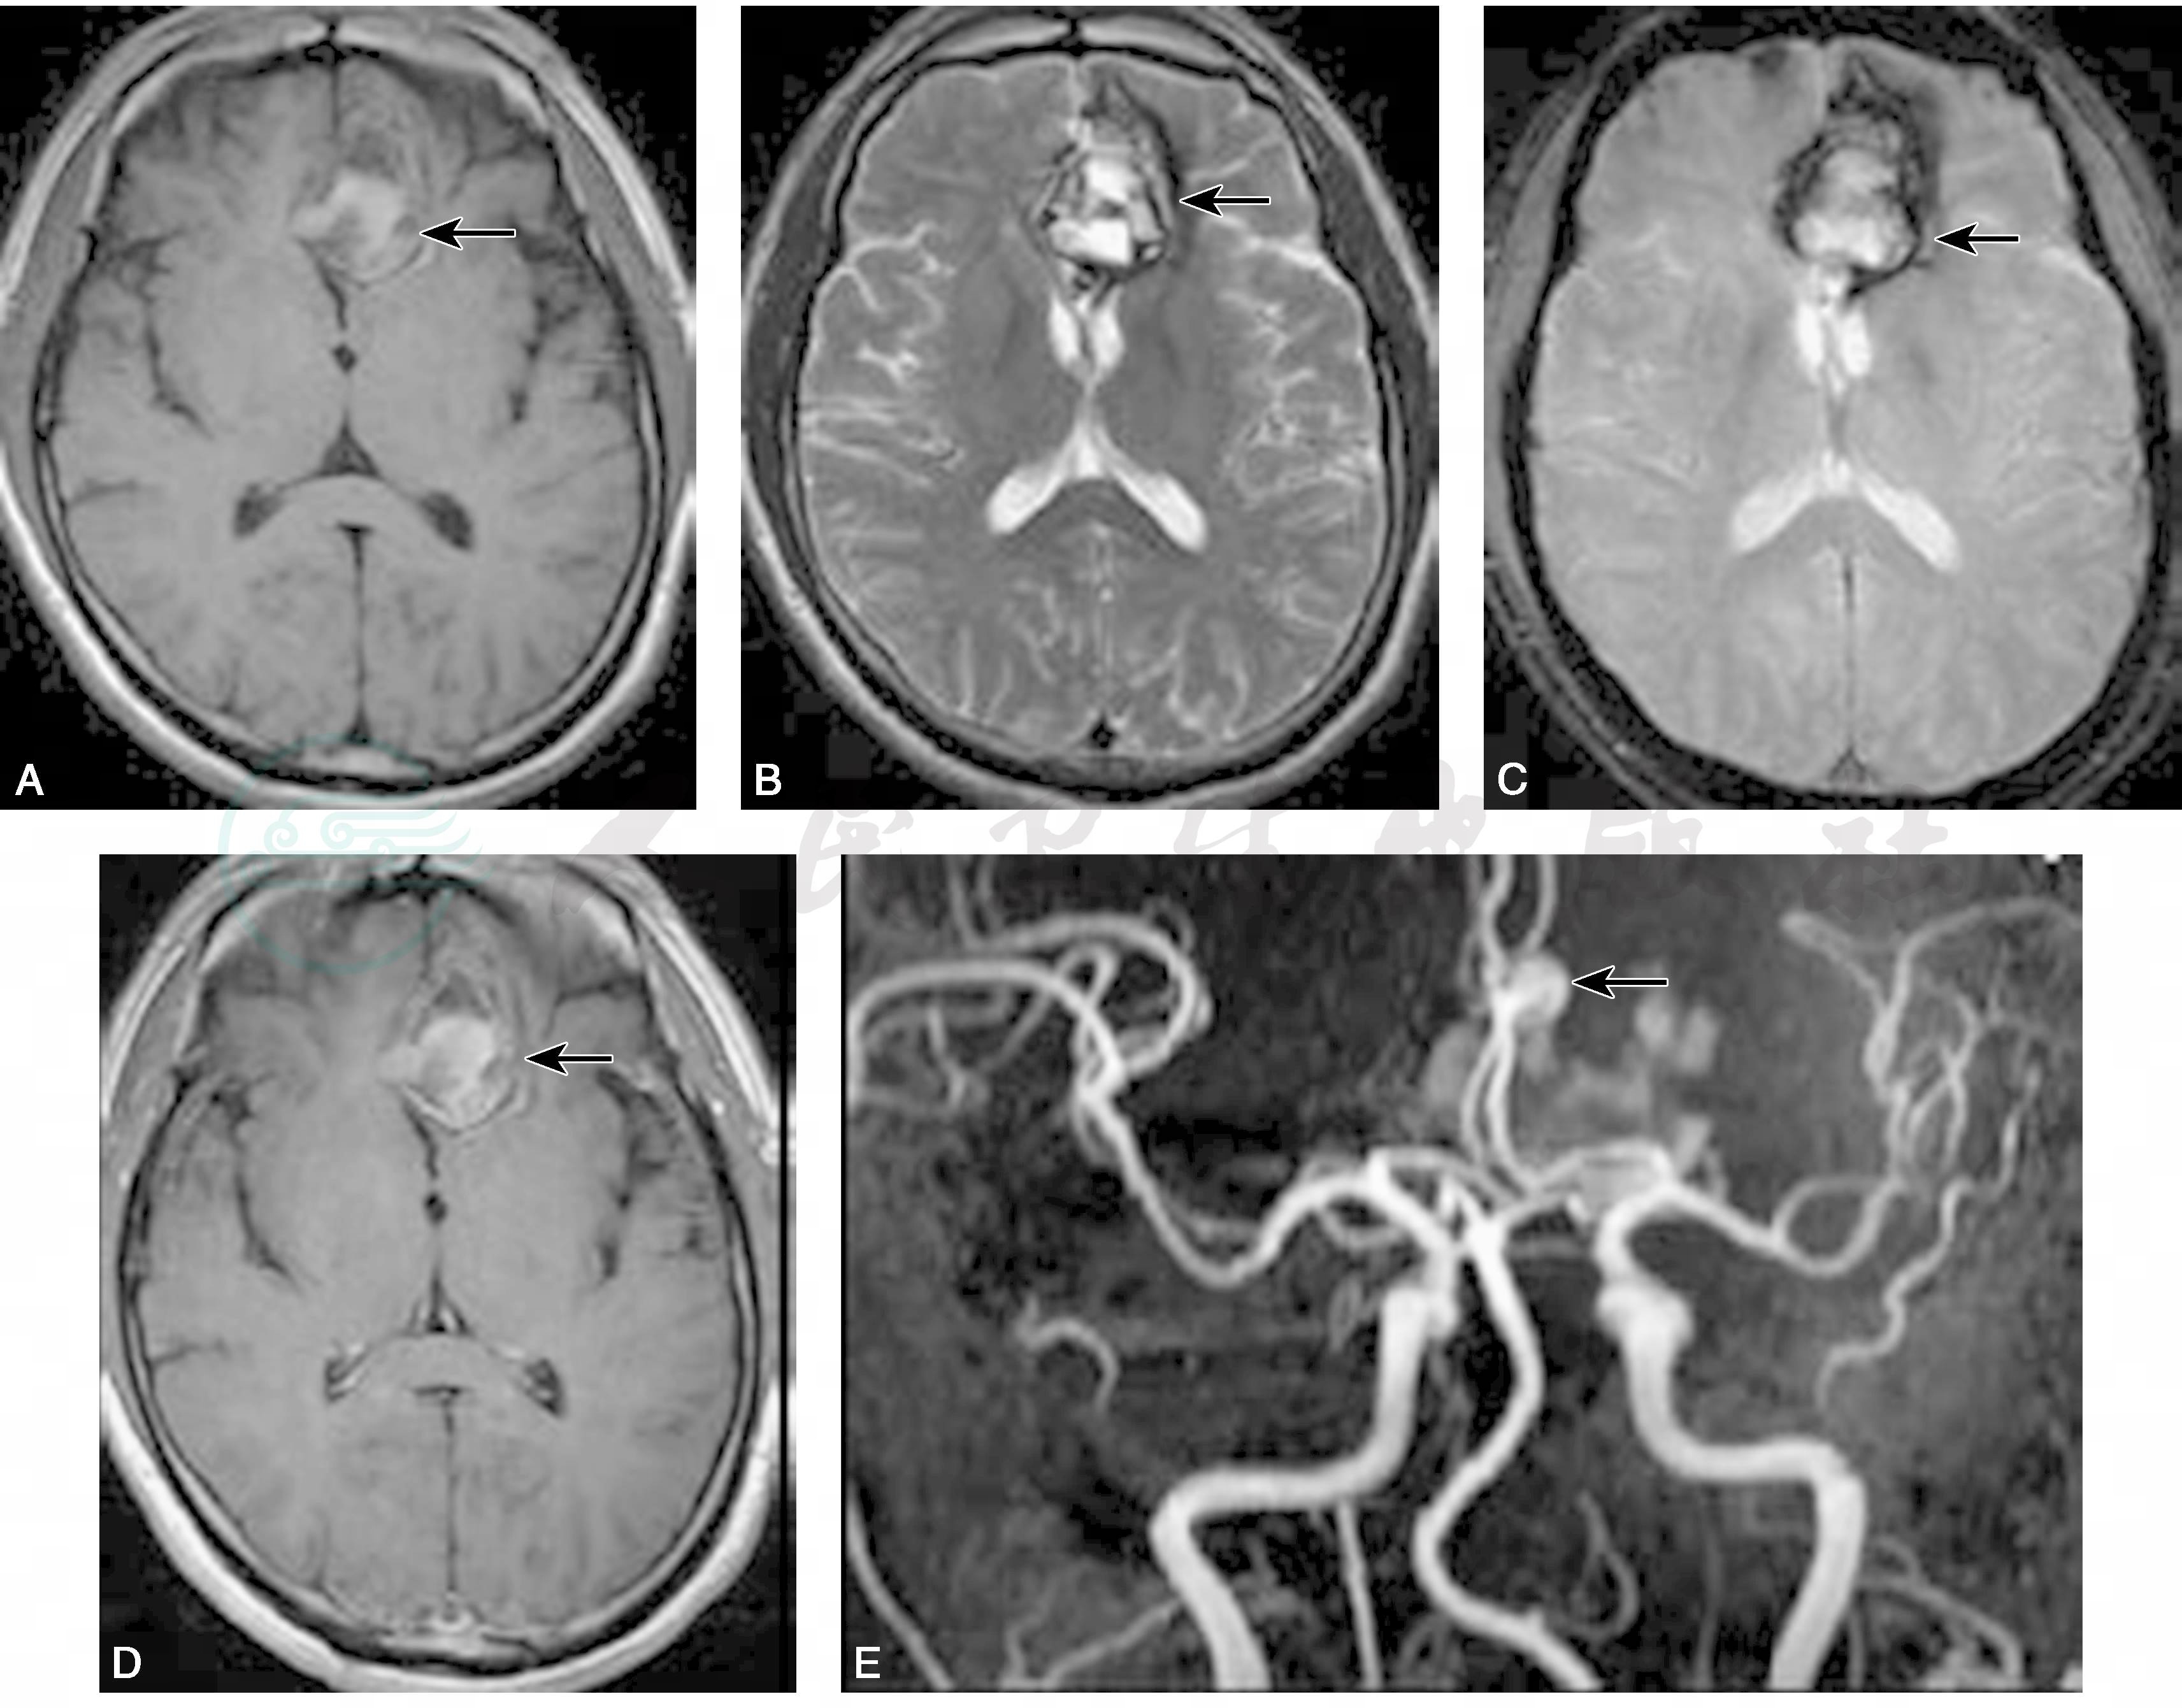

血、尿、便常规、凝血象未见明显异常;血生化全套:肌酐111.0μmol/L,尿酸490.0μmol/L,血钠、钾、氯正常;血同型半胱氨酸35.34μmol/L;超敏C反应蛋白0.9mg/L;肿瘤标志物:正常。腹部B超示:肝胆胰脾肾未见异常。颅脑MRI示:左侧额底近中线处出血灶,颅脑MRA检查示左侧大脑前动脉瘤(见图7)。于2009年6月10日行颅脑DSA检查证实为右侧大脑前动脉A3段动脉瘤,大小约7mm×8mm(图8)。

图7 2009年6月2日颅脑MRI检查示左额近中线不规则混杂短长T1(A)T2(B)信号影,梯度回波见含铁血黄素沉积(C),病变无异常强化(D),MRA检查示左侧大脑前动脉动脉瘤(E)(箭头)